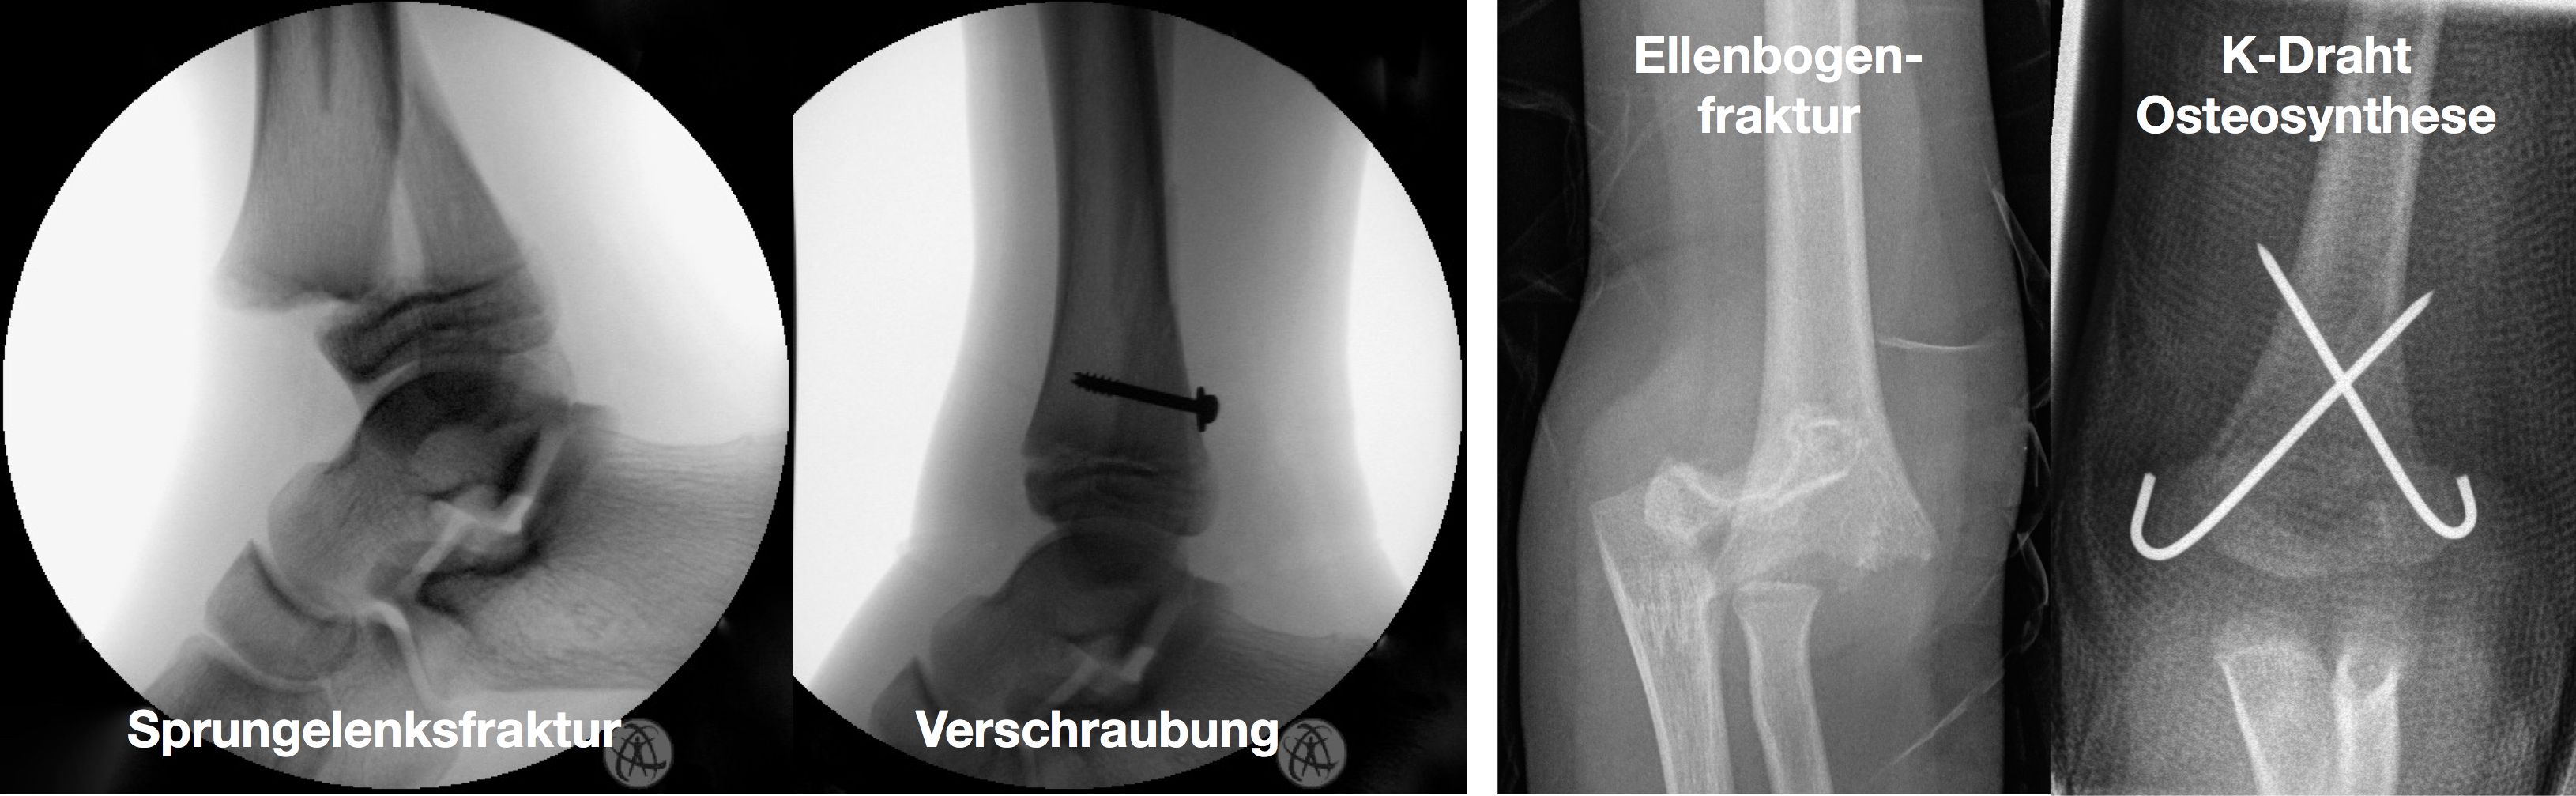

Einige Frakturen müssen auf Grund ihrer Achsabweichung operiert werden. In einer Narkose wird die Fraktur eingerichtet und ggf. mit Metall stabilisiert. Dazu stehen eine Reihe von Methoden (Osteosynthesen) zur Verfügung, die speziell für Kinder entwickelt wurden, um Wachstumsfugen zu schonen und nicht zu verletzen: Die ESIN (elastisch stabile intramedulläre Nagelung) hat sich als minimal invasives Standardverfahren zur Stabilisierung von Schaftfrakturen der großen Röhrenknochen (Unterarm, Oberarm, Unterschenkel, Oberschenkel) etabliert. Die Implantate können über winzige Schnitte eingebracht werden, eine gipsfreie Nachbehandlung ist ein weiterer entscheidender Vorteil.

Kirschner-Draht-Osteosynthese

Andere Verfahren der operativen Frakturversorgung im Kindesalter sind die Kirschner-Draht-Osteosynthese, die Verschraubung, der Fixateur und die Plattenosteosynthese. Metallentfernungen werden ambulant durchgeführt, Nachuntersuchungen zum Ausschluss etwaiger Wachstumsstörungen erfolgen in unserer Frakturensprechstunde.